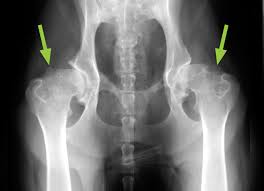

Arthritis And The Aging Dog Dogtime from www.dogtime.com A degenerative disease, arthritis most often results from everyday wear and tear on the joints. In fact, the older your dog gets, the more the chances increase. You're more sedentary, and inactivity can lead to weight gain. Both primary and metastatic bone tumors occur infrequently in cats. Veterinarians must also radiograph the dog's chest to screen him for secondary tumors that may have spread. Lameness or a distinct swelling may be noted. It is a cartilage type tumor, and it's usually not as malignant as osa. Dogs aged seven and above have a 65 percent chance of suffering from this disease.

Dog Hip Pain And Bone Diseases Causing Joint And Leg Pain And Limping In Growing Canines from www.pethealthnetwork.com It's an extremely deadly and aggressive form of cancer that. It is very painful because the tumor is destroying normal bone and stretching the tissue that lines the. Here are the best ways to manage your dog's osteoarthritis. In order to preserve your pet's quality of life, visit the veterinarian to receive advice and arthritis therapy. Bone cancer in dogs also known as osteosarcoma is an aggressive disease that may result in limb amputation or the removal of the affected bone. Common causes of joint pain include fractures, congenital disorders, hormonal conditions, arthritis, cancer, lyme disease, and injuries. Occasionally, dogs will exhibit a mass growth on their body or a painful inflammation around the site of the tumor. It is a cartilage type tumor, and it's usually not as malignant as osa.